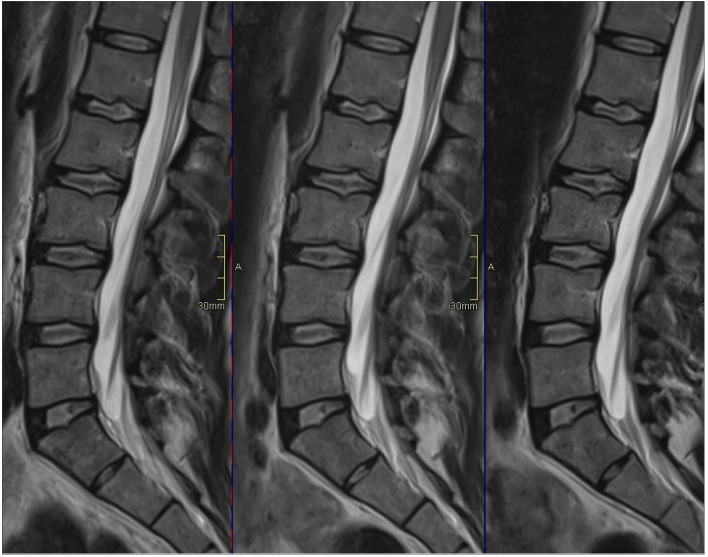

PURPOSE The increasing interest of endplate and Modic changes as potential pain generators in low back pain (LBP), along with advancement of functional quantitative magnetic resonance imaging (MRI) techniques, makes it important to characterize the vertebral dynamic behavior in detail. This study aims to perform characterization of the dynamic behavior of the vertebral bodies (VB) by investigating the VB diurnal variation in T2-relaxation time in a cross-sectional asymptomatic group of individuals. METHODS T2-mapping of 30 VBs (L1-L5) in six healthy volunteers (mean age, 40 years; range, 29-65 years) was performed with a 1.5 Tesla MRI at three time points over the day (7 am, 12 am, 5 pm). Volumetric regions of interest were segmented manually to determine VB T2-relaxation time, which was compared between the three time points. RESULTS On a group level only small and not significant diurnal VB variation was detected (all P >.10), with median T2 (ms) (quartiles; Q1, Q3) at the three time points 88.7 (84.1, 99.1), 87.3 (85.0, 96.1) and 87.8 (84.4, 99.2). However, in some VBs up to 7% increase respectively 9% decrease in T2-relaxation time was found during the day. Further, there was a relatively large variation between the individuals in absolute VB T2-relaxation times (range 73.2-108.3 ms), but small differences between the VBs within an individual. CONCLUSION This first T2-mapping study of the VB signal dynamics, in repeated investigations during one day, display variation in T2-relaxation time in specific individual VBs but were negligible on a group level. The result may be of importance when evaluating patients with spinal pathologies and suggest further examinations of dynamic changes not only of the disc but also vertebrae.

Abstract Image